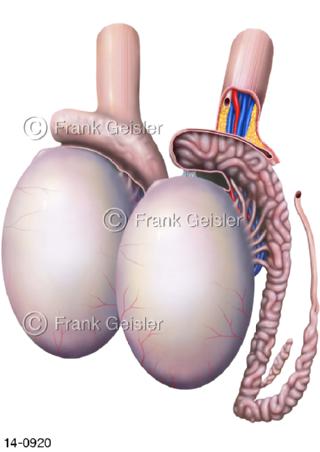

Bildergalerie Urogenitalsystem

Bilder zum Urogenitalsystem mit Urogenitalorgane, Urogenitaltrakt, zum Harn- und Geschlechtsapparat, Harnorgane und Geschlechtsorgane, Organe der Harnwege und der Fortpflanzung, Harnorgane und Geschlechtsorgane im männlichen und weiblichen Urogenitalsystem